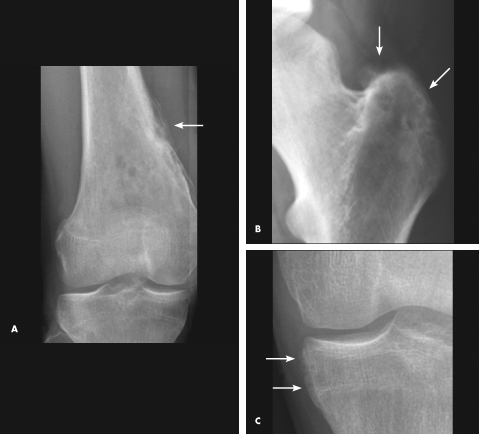

osteomyelitis

Nancy Pan, MD; Robert Schneider, MD; Austin Fragomen, MD; Kyriakos A. Kirou, MD

<P><IMG style="MARGIN: 5px; FLOAT: left" src="/sites/default/files/images/Screen%20shot%202012-04-09%20at%2011.49.54%20AM.png" width=103 height=88>18-year-old boy with a long...